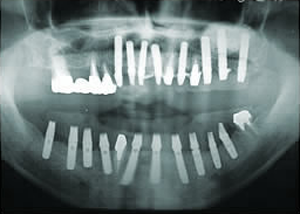

5.終了時レントゲン

治療完了

平成19年5月1日

(治療期間:2年10ヶ月)